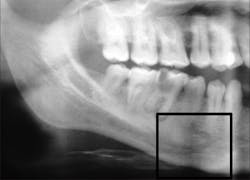

No. 2: Violations of a branch of a bifid or trifid mandibular canal

The IAC is typically described as a singular canal4 containing the neurovascular bundle that clinicians know not to violate, and a 2 mm “safety zone”5 has been described when placing dental implants. It is now known that multiple smaller branches of the IAC can occur that run parallel to the main trunk of the canal.6 Up to 40% of the nerve can branch off the main canal, and if these branches are large enough, a secondary or even tertiary canal can result (figure 2).

Multiple branches of the mandibular canal often go unrecognized, because many dentists are unaware of this anatomic variation even though the canals may be visible on a panoramic radiograph or CT scan. Violations of this secondary/tertiary canal resulting in pain post-implant placement have been described in the literature.7